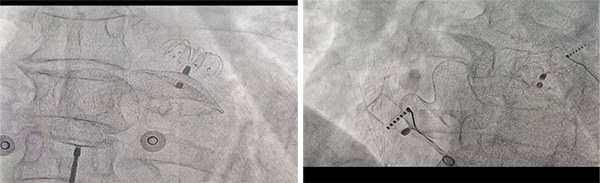

植入过程:通过渐进式植入固定盘,在右肩位及肝位确定固定盘抵达预定位置且完全展开。

植入过程:释放封堵盘后造影可见下缘存在少量残余分流,通过超声观察为靠近二尖瓣位置贴靠不佳,但术中评估钢缆拉力明显,预估释放后能够有效贴合,牵拉15s无位移,可以释放。

释放过程:释放封堵器的过程能够看到明显贴靠,通过造影发现先前的残余分流消失,未见新增的残余分流。

房缺封堵器植入后推拉稳定,形态良好,通过经胸彩超未见残余分流,遂释放封堵器。